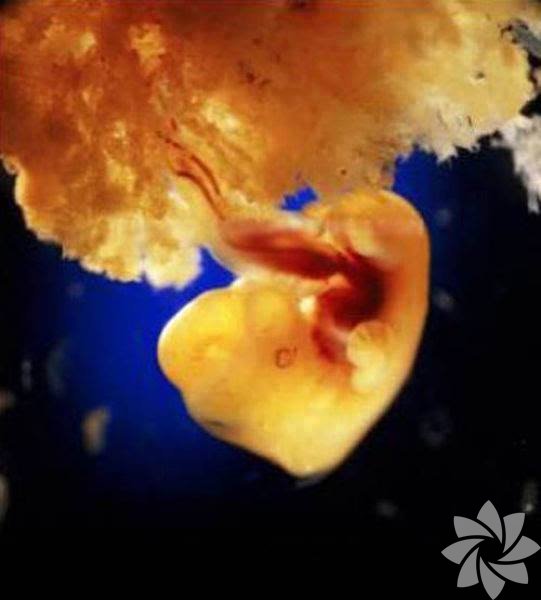

6. hafta. Artık kollar, bacaklar ve baş belirginleşti. Plasenta da bebekle birlikte büyüyor.

40 günlük plasenta.